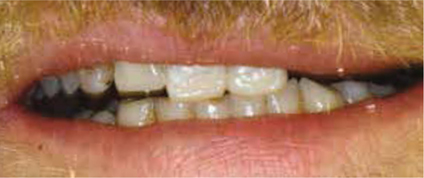

Dit traject van circa 3 jaar leverde een eindresultaat op zoals getoond op de afbeeldingen 27-44. De heer H. was daar uitermate tevreden mee en werd terugverwezen naar zijn huistandarts.

Afb. 45

De heer H. na afbehandeling in 2011: er is meer veranderd dan alleen de mondsituatie.

Afbeelding vergroten